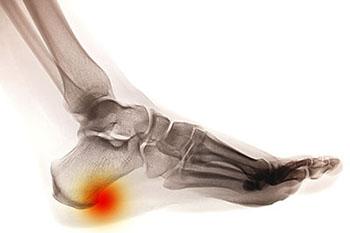

Heel spurs are brought upon by a calcium deposit that causes a bony protrusion on the underside of the heel bone. It normally forms over time and can best be diagnosed through an x-ray examination. Heel spurs are commonly linked with plantar fasciitis, an inflammation...